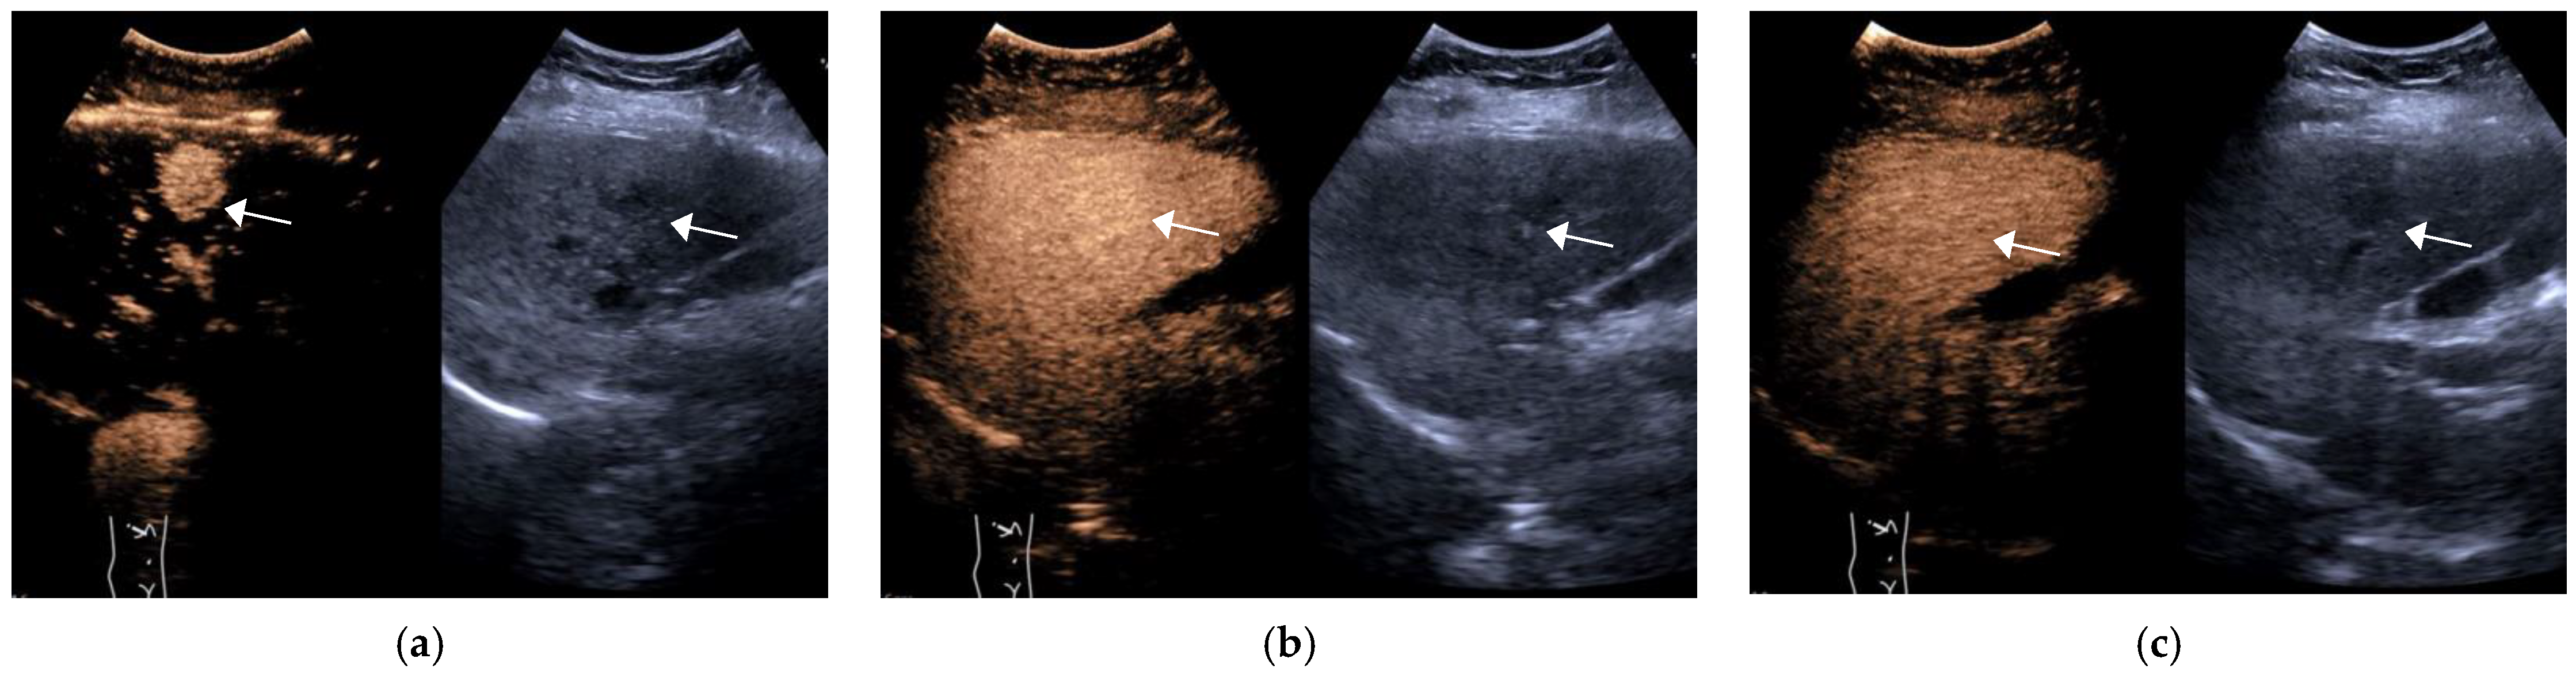

Figure 1.

Female, 55 years old, LR-4 category. A slightly hypoechoic lesion of approximately 2.6 × 2.5 cm in size (arrow) is seen in S6, with hyperenhancement in the arterial phase (a) and no significant washout in the portal phase (b) and delayed phase (c). The final pathological diagnosis is highly differentiated HCC.